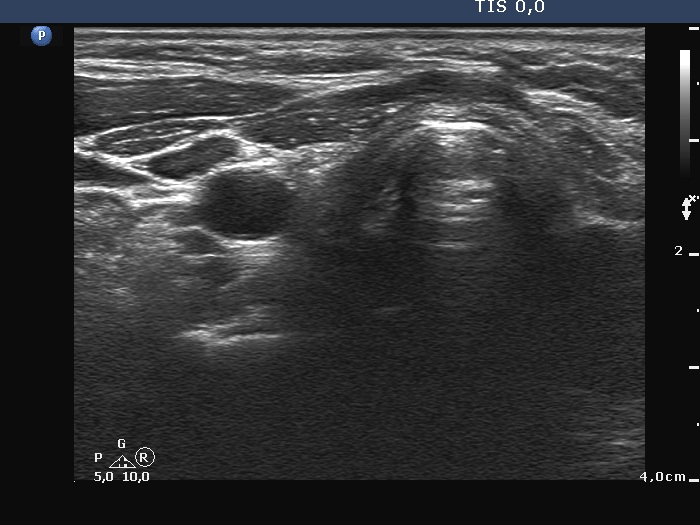

Ultrasonography. There was no thyroid tissue in the thyroid beds. Approximately 7 cm above the thyroid in the left side of the neck there were multiple, moderately hypoechoic lesions which presented tiny cystic areas. They had vascularity but did not have capsule.